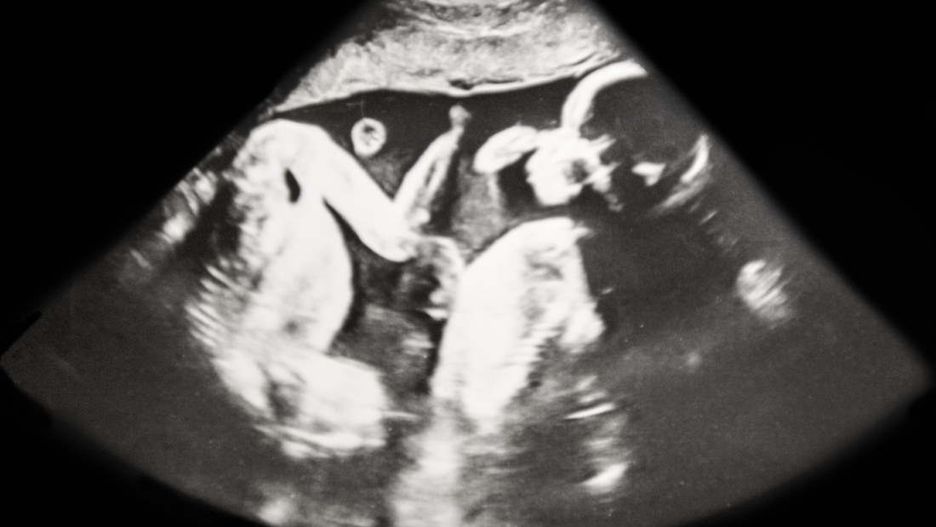

Gina i Craig ucieszyli się, gdy dowiedzieli się, że zostaną rodzicami trojaczków. W 24. tygodniu ciąży poznali nawet płeć wszystkich dzieci. Badanie USG wykazało, że mama nosi w brzuchu dwie dziewczynki i jednego chłopca. Potem powtarzano je pięciokrotnie i za każdym razem potwierdzano płeć dzieci.

"Rozumiem, dlaczego USG przyniosło pomyłkę, bo dzieci ciągle się ruszały. Zawsze jakaś ręka lub noga przeszkadzała" - mówi mama.